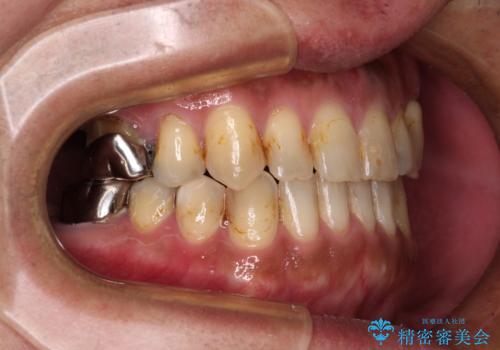

前歯の反対咬合をワイヤー矯正で改善して噛みやすく

前歯の反対咬合が改善する過程では、奥歯が咬みにくくなるため、食事では辛い思いをされていたようです。

矯正治療後は安定した咬み合わせとなり、顎の違和感がなくなったとのことでした。

今後はむし歯や銀歯を治療していく予定です。